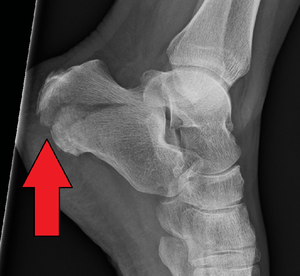

Conventional radiography is usually the initial assessment tool when calcaneal fracture is suspected. Recommended x-ray views are (a) axial, (b) anteroposterior, (c) oblique views and (d) views with dorsiflexion and internal rotation of the foot. However, conventional radiography is limited for visualization of calcaneal anatomy, especially at the subtalar joint. CT Scan is currently the imaging study of choice for evaluating calcaneal injury and has substituted conventional radiography in the classification of calcaneal fractures.[11] Axial and coronal views are taken for proper visualization of the calcaneus, subtalar, calcaneocuboid and talonavicular joints.

Calcaneal fractures are categorized into two types: Intra- and Extrarticular fractures on the basis of subtalar joint involvement. Intrarticular fractures are more common and involve the posterior talar articular facet of the calcaneus. The Sanders classification groups these fractures into four types, based on the location of the fracture at the posterior articular surface. Extrarticular fractures are less common, and located anywhere outside the subtalar joint.[11] Extrarticular fractures are categorized depending on whether the involvement of the calcaneus is anterior (Type A), Middle (Type B) or Posterior (Type C).